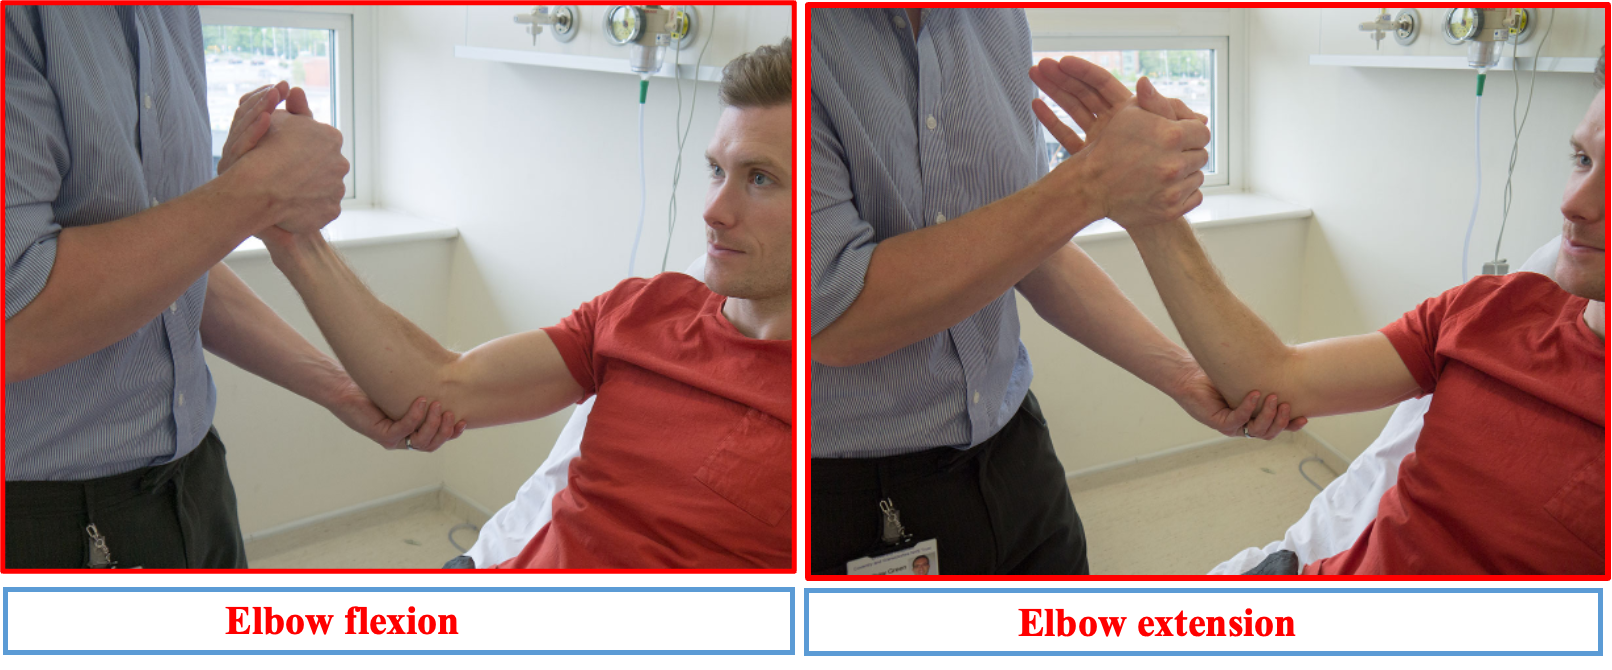

UL MOTOR EXMINATION

Tone Start proximally at the shoulder, feeling how easy the joint is to move passively. Then move down to the elbow, wrist and hand joints, again assessing each one’s tone in turn.

Power

Start at the shoulder asking the patient to abduct and adduct against your hand so you can assess how much force they can overcome. Do the same for flexion and extension at the elbow and wrist, as well as the fingers; also checking abduction and adduction of the thumb.